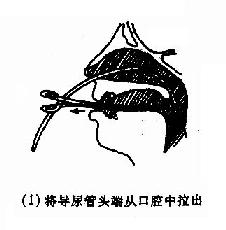

(2)后鼻孔填塞法(postnasal packing):先将凡士林纱条或消毒纱布卷迭成块形或圆锥形,长约3.5cm,直径约2.5cm,用粗线缝紧,两端各有约25cm长的双线,消毒备用。填塞时先收缩和表麻鼻腔粘膜,咽部亦喷有表面麻醉剂。用导尿管由前鼻孔沿鼻腔底部插入直达咽部,用镊子将导管从口腔拉出,导尿管尾端则留于前鼻孔外,再将填塞物上的双线系于导尿管,此时将填塞物由口腔送入鼻咽部,填塞于后鼻孔。为了减少患者痛苦,可用弯止血钳将填塞物在明视下送到悬壅垂的后上方,再将导尿管的鼻端向外拉紧。最后在前鼻孔处用一纱布球,将双线系于其上,以作固定,口腔端的线头可剪短留在口咽部,便于以后取出填塞物时作牵拉之用。后鼻孔填塞后,一般都需加行鼻腔填(图4-7)。鼻腔填塞物应于24~48小时内取出或更换,以防引起鼻窦及中耳感染等并发症。

图4-7 后鼻孔填塞法